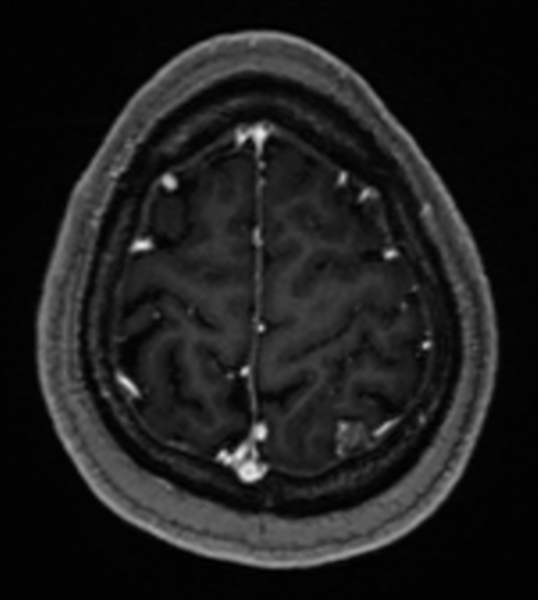

入院后,医院为她进行了详尽的颅脑MRI增强及头颅CT薄扫检查,结果显示其病变位于左侧顶上小叶,病变对脑组织压迫明显(病变周围脑组织CBF灌注明显降低、较对侧脑回体积明显减小),且与左侧大脑上静脉紧密相关,动态视频脑电图分析进一步提示病灶周围脑组织存在异常放电。

术前MRI轴位图像

术前MRI提示左侧中央后回较对侧稍小。